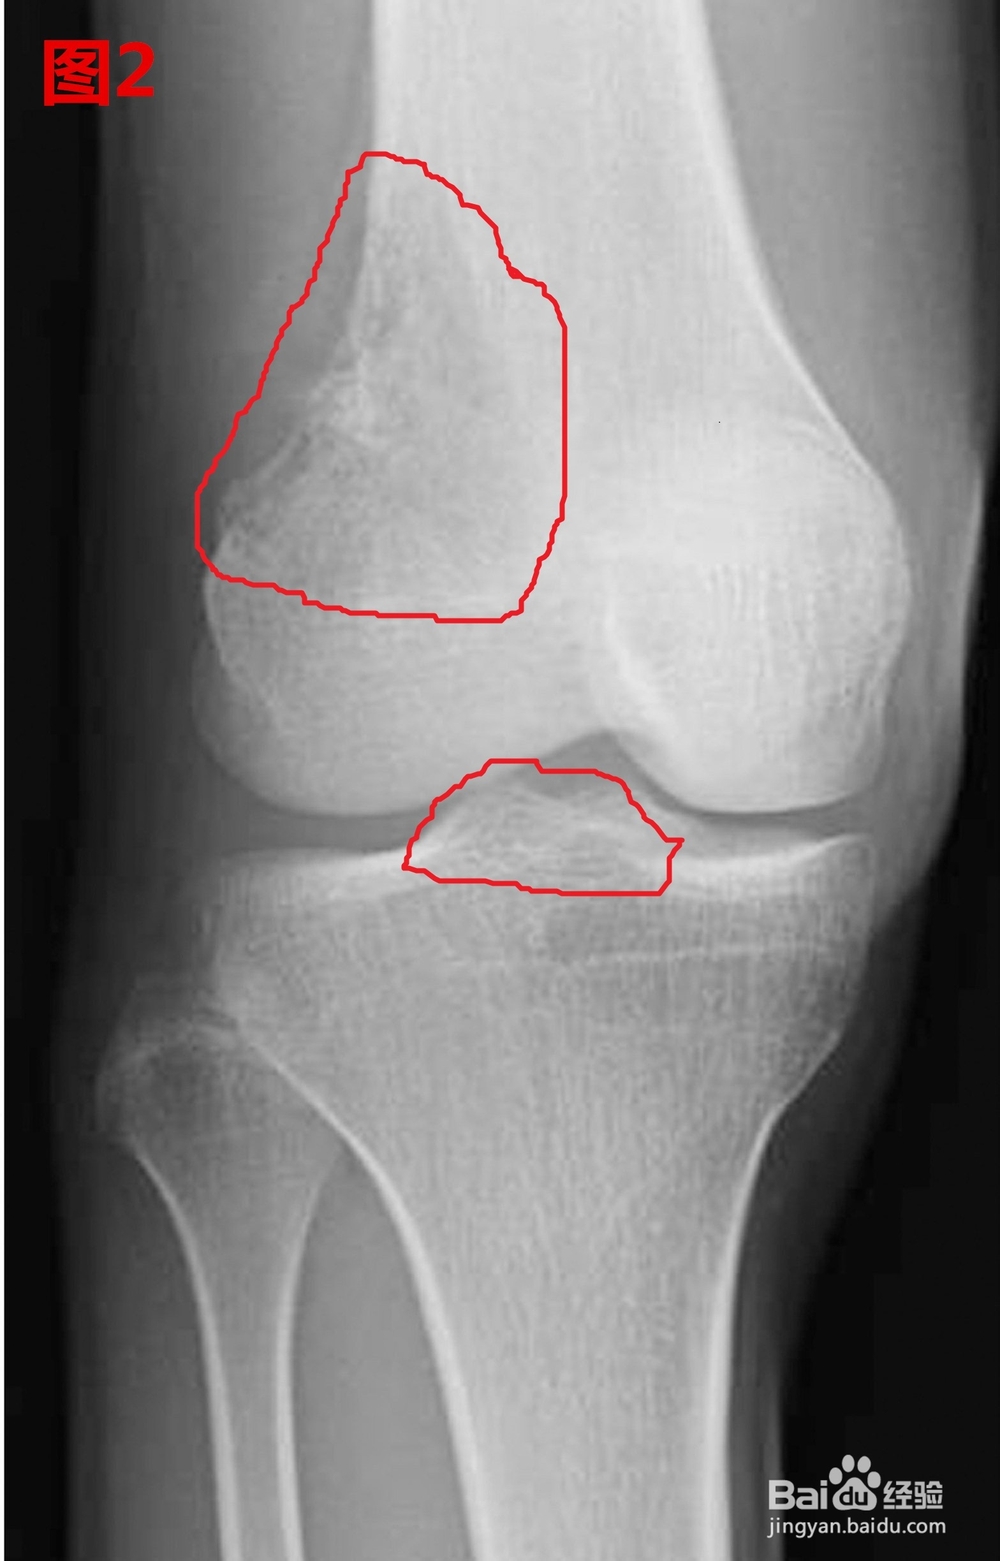

1、我们在放射片里会看到这样的地方,这就是骨刺.